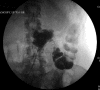

The management of enterocutaneous fistulas continues to be a challenging postoperative complication. Understanding the anatomy of the fistula optimizes its evaluation and management. Diagnostic radiology has always played an important role in this task. The use of plain radiography with contrasted studies and fistulograms is well documented in the earliest investigations of fistulas and they continue to be helpful techniques. The imaging techniques have evolved rapidly over the past 15 years with the introduction of cross-sectional imaging, ultrasound and endoscopy. The purpose of this chapter is to review both the diagnostic and therapeutic roles of fistulograms, small bowel follow-through, computed tomography, magnetic resonance imaging, ultrasound, and endoscopy in the setting of acquired enterocutaneous fistulas.